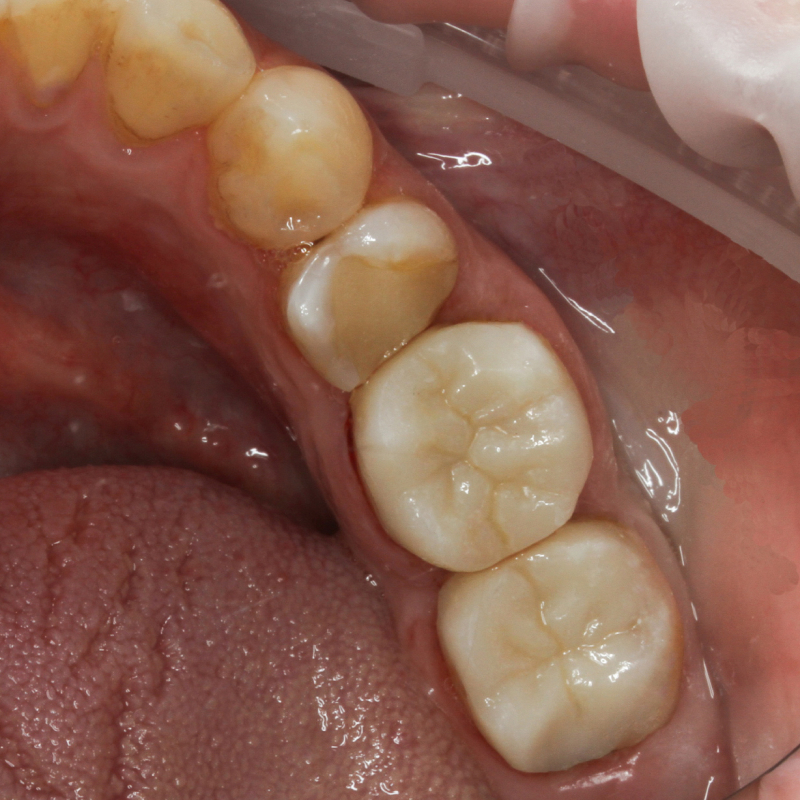

Восстановление зубов 3.6, 3.7 керамическими накладками OverlayСмотреть работуСрок лечения:2 посещения длительностью 1 час с интервалом в 1 неделюСумма лечения:36 000 р.